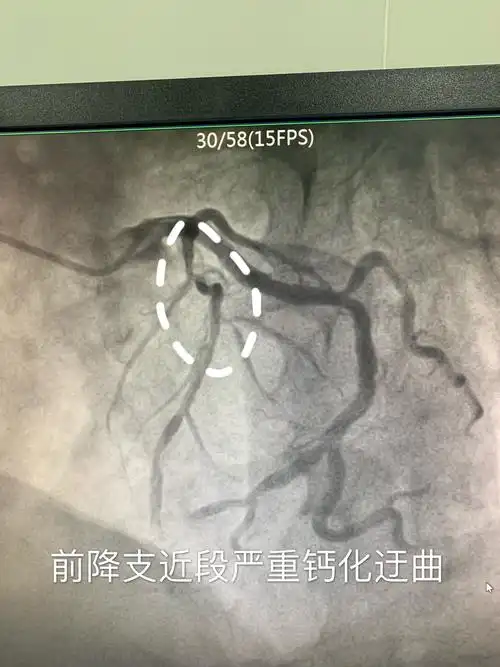

造影提示:前降支近段临界病变狭窄60-70%,中段狭窄40%伴肌桥.

完善各项术前准备造影结束,冠脉造影显示前降支近段重度狭窄伴严重

冠状动脉造影示前降支中段局限性狭窄约90%